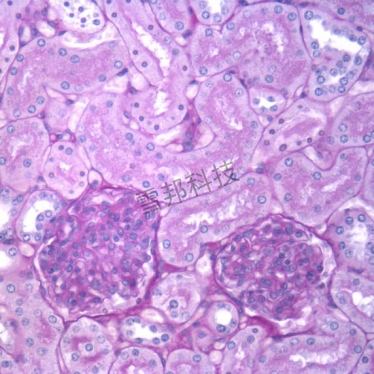

PAS染色法(Periodic Acid-Schiff stain)在组织学上,主要用来检测组织中的糖类。过碘酸把糖类相邻两个碳上的羟基氧化成醛基,再用Schiff试剂和醛基反应使呈现紫红色。